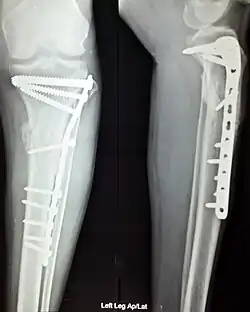

Bone malrotation refers to the situation that results when a bone heals out of rotational alignment from another bone, or part of bone. It often occurs as the result of a surgical complication after a fracture where intramedullary nailing (IMN) occurs,[1] especially in the femur and tibial bones, but can also occur genetically at birth. The severity of this complication is often neglected due to its complexity to detect and treat,[1] yet if left untreated, bone malrotation can significantly impact regular bodily functioning, and even lead to severe arthritis. Detection throughout history has become more advanced and accurate, ranging from clinical assessment to ultrasounds to CT (computed tomography) scans. Treatment can include an osteotomy, a major surgical procedure where bones are cut and realigned correctly, or compensatory methods, where individuals learn to externally or internally rotate their limb to compensate for the rotation. Further research is currently being examined in this area to reduce occurrences of malrotation, including detailed computer navigation to improve visual accuracy during surgery.[2]

Bone malrotation predominantly occurs after an injury where a bone is fractured, however malrotation can genetically occur during foetal development. It usually occurs during a surgery which involves intramedullary nailing, which is the insertion of metal rods and nails to stabilise bones. Nailing is used as it requires minimal surgical dissection, less disruption of the fracture hematoma and allows faster functionality to a patient post-surgery.[1][3] However, due to the semi-closed nature of IM, it is impossible to correct under direct vision, so there is less rotational control compared to traditional open methods such as plate fixation.[3] As a result, in many cases of intramedullary nailing, the bone is misaligned which causes malrotated regrowth. This torsional error is a major problem for femoral and tibial fractures, and occurs in 17 to 35% of patients who receive these surgeries,[4] and up to 40% of femur fracture patients.[1]

In extreme cases, the malalignment can be treated by means of a derotational osteotomy which is a major surgical procedure.[3] It can be conducted around the existing intramedullary fixtures, but it usually requires a subtrochanteric osteotomy, which is an invasive surgical approach where bone is cut and realigned. As this is a major procedure, it is beneficial if discovered early, before callus has set, and consequently, patients should be assessed for malrotation in the early post-operative period and a CT scan should occur if abnormalities are found.[5] Correct measurement of bone malalignment with a CT scan is vital when considering an osteotomies in fixing rotational deformities, as torsional differences below 15 degrees are often easily compensated for with non surgical treatment.[3] Revision surgery should be avoided, if not necessary, as implementing femoral nails for a second time leads to higher rates of problems such as infection, nonunion, or nail destabilisation due to overlapping holes for the interlocking screws.[10]